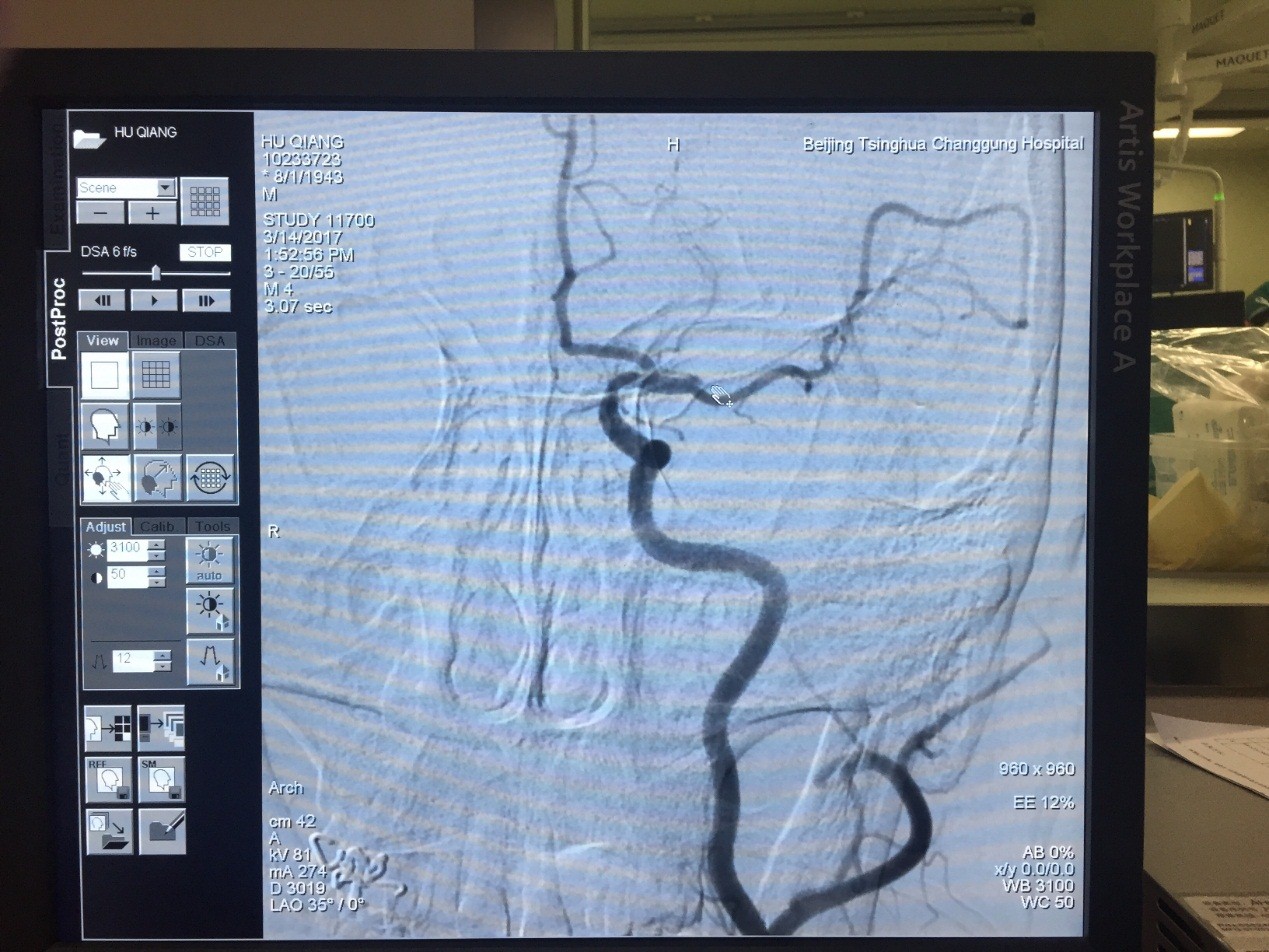

神经内科与外科、急诊通力合作,在患者到院仅45分钟时就给予了静脉rt-PA治疗。随后神经内科李秀丽医师和魏宸铭医师密切注意患者病情变化,反复评价神经功能,发现患者静脉溶栓治疗后神经功能未获得显著恢复,遂立即转入神经外科介入手术室。神经外科苏伟医师等介入室医护人员再接再厉,手法娴熟,13:30接入患者,13:50完成DSA检查,证实患者为左侧大脑中动脉上干起始段闭塞,14:55完成动脉取栓治疗,患者血管再通。此时患者原本瘫痪的右手可以自行抬起并握拳了。

图为患者由急诊转入介入室行血管内治疗

图为患者DSA显示左侧大脑中动脉上干起始端闭塞